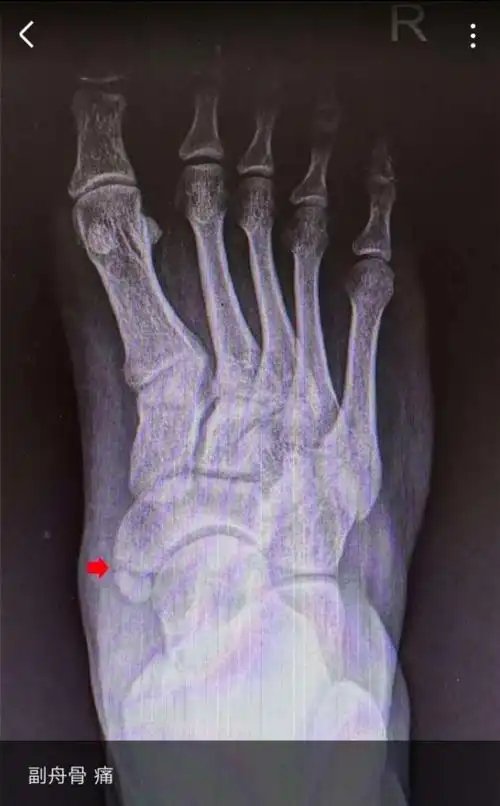

带您了解足"副舟骨"综合征